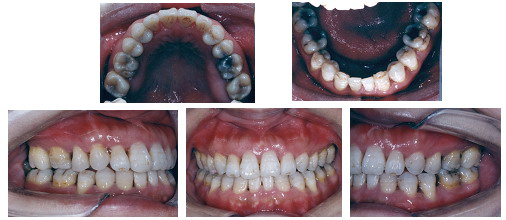

以下是一名38岁女性反合患者的病例,治疗前存在前牙反合、牙弓形态异常、牙弓左右不对称同时伴有颜面骨骼发育异常,面部比例失调,唇突度不协调以及全口不同程度的牙周炎症牙槽骨丧失、上颌尖牙早失,治疗难度很大。经过牙周和正畸的共同努力,在控制牙周炎症之后拔除两颗下切牙,采用目前国际上最流行的MBT矫治技术,经过15个月的治疗,达到了理想的治疗效果。

治疗完成一年复查